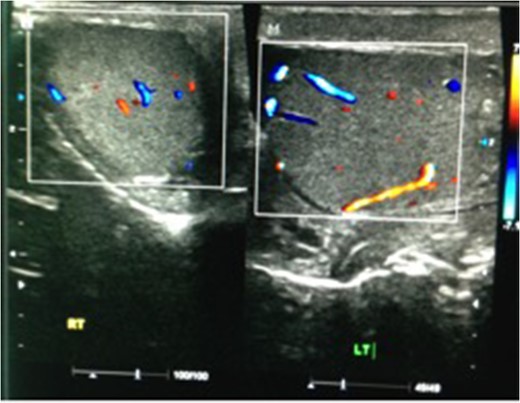

We present a case of a 37-year-old man presented to the Emergency department with a 3-day history of left testicular pain. He had no chronic illnesses and was not immunocompromised. The pain was associated with mild storage lower urinary tract symptoms. He was sexually active but had no previous sexually transmitted diseases and no urethral discharge. He had no history of trauma and had not had any similar episodes before. His examination revealed a swollen tender left testicle; equivocal for testicular torsion. A Doppler ultrasound was done which revealed increased flow to the left testicle with no evidence of testicular torsion (Fig. 1). The patient was subsequently discharged on oral ciprofloxacin, analgesia and instructed to perform scrotal elevation. The patient subsequently presented 6 h later with worsening of his pain and was reviewed and re-imaged with a color Doppler. At this time, imaging findings demonstrated reversal of diastolic flow a feature suggesting impending infarction, along with other features of acute inflammation (Fig. 2). The patient was taken to the operating room and a scrotal exploration was performed. No evidence of torsion was identified. A congested testicle was observed. No evidence of infarction or abscess formation was seen. Day 1 post-operatively the patient continued to have left sided testicular pain, now associated with lower abdominal pain. A KUB ultrasound and a repeat scrotal ultrasound were performed. These demonstrated absent flow in the left testicle (Fig. 3). On repeat exploration a dusky blue testicle was found and a left orchidectomy performed. Testicular histopathological analysis demonstrated features suggestive of acute necrotizing inflammation of the testes and epididymis as well as the spermatic cord and its vessels. Cultures of the urine subsequently showed significant growth of Escherichia coli.

Repeat ultrasound scan 6 h later showing reversal of diastolic flow.